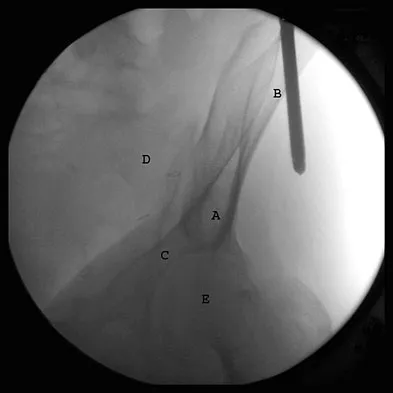

What letter in Figure 33 marks the correct starting point for a transiliac pelvic screw?

Explanation